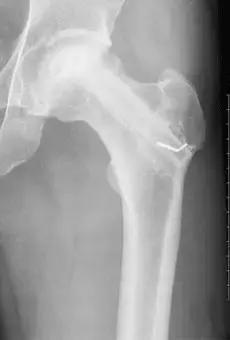

股骨头坏死Ⅰ期。治疗时间约半年以上的时间,早期及时诊断并按医嘱治疗,一个疗程可以有明显好转,股骨头不仅形态完好而且X线片显示死骨区吸收,骨密度恢复。疼痛缓解、股骨头基本可保住。

股骨头坏死Ⅱ期。治疗时间约十个月以上,早期及时诊断并按医嘱可使坏死囊变区的新骨再生。X片显示有新生骨小梁通过。

股骨头坏死Ⅲ期。治疗时间约一年以上,三个疗程后死骨已全部吸收,大部分骨小梁基本上通过,疗程结束后股骨头死骨全部吸收完,股骨头轮廓及部分的骨质变化清晰。

股骨头坏死Ⅳ期。治疗时间约一年半以上,坏死骨完全吸收,也能够将死骨区吸收。通过大量的新生骨小梁的增添、填植,股骨头能够重愈,但股骨头形态不饱满、圆滑。